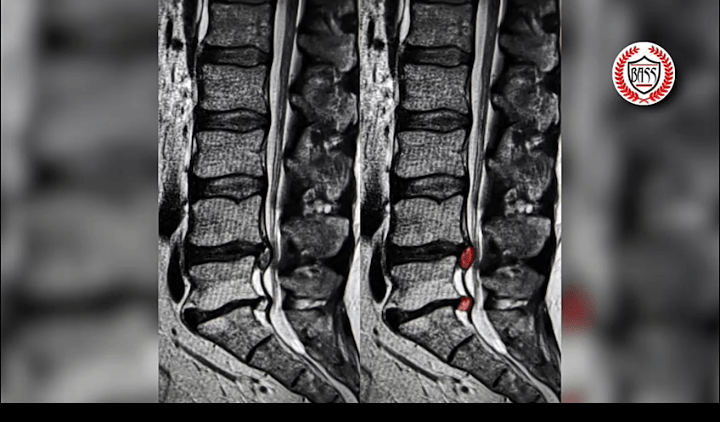

The management of spine patients can be easy or complex depending on the condition presented and the options for management. This was brought to light for me recently when I saw a woman with severe back and bilateral leg pains. She demanded surgical treatment and therefore freedom from pains. Indeed, she had been offered surgery at another facility. She looked in real trouble, but the clinical examination was normal. Further, her MRI scan did not show a significant lesion responsible for the pains.

You see, we as spine surgeons require a specific target for surgical intervention. We need to know where we are going to do the operation, what we will do when we get there and finally, that the exercise will be justified, resulting in good outcome for the patient.